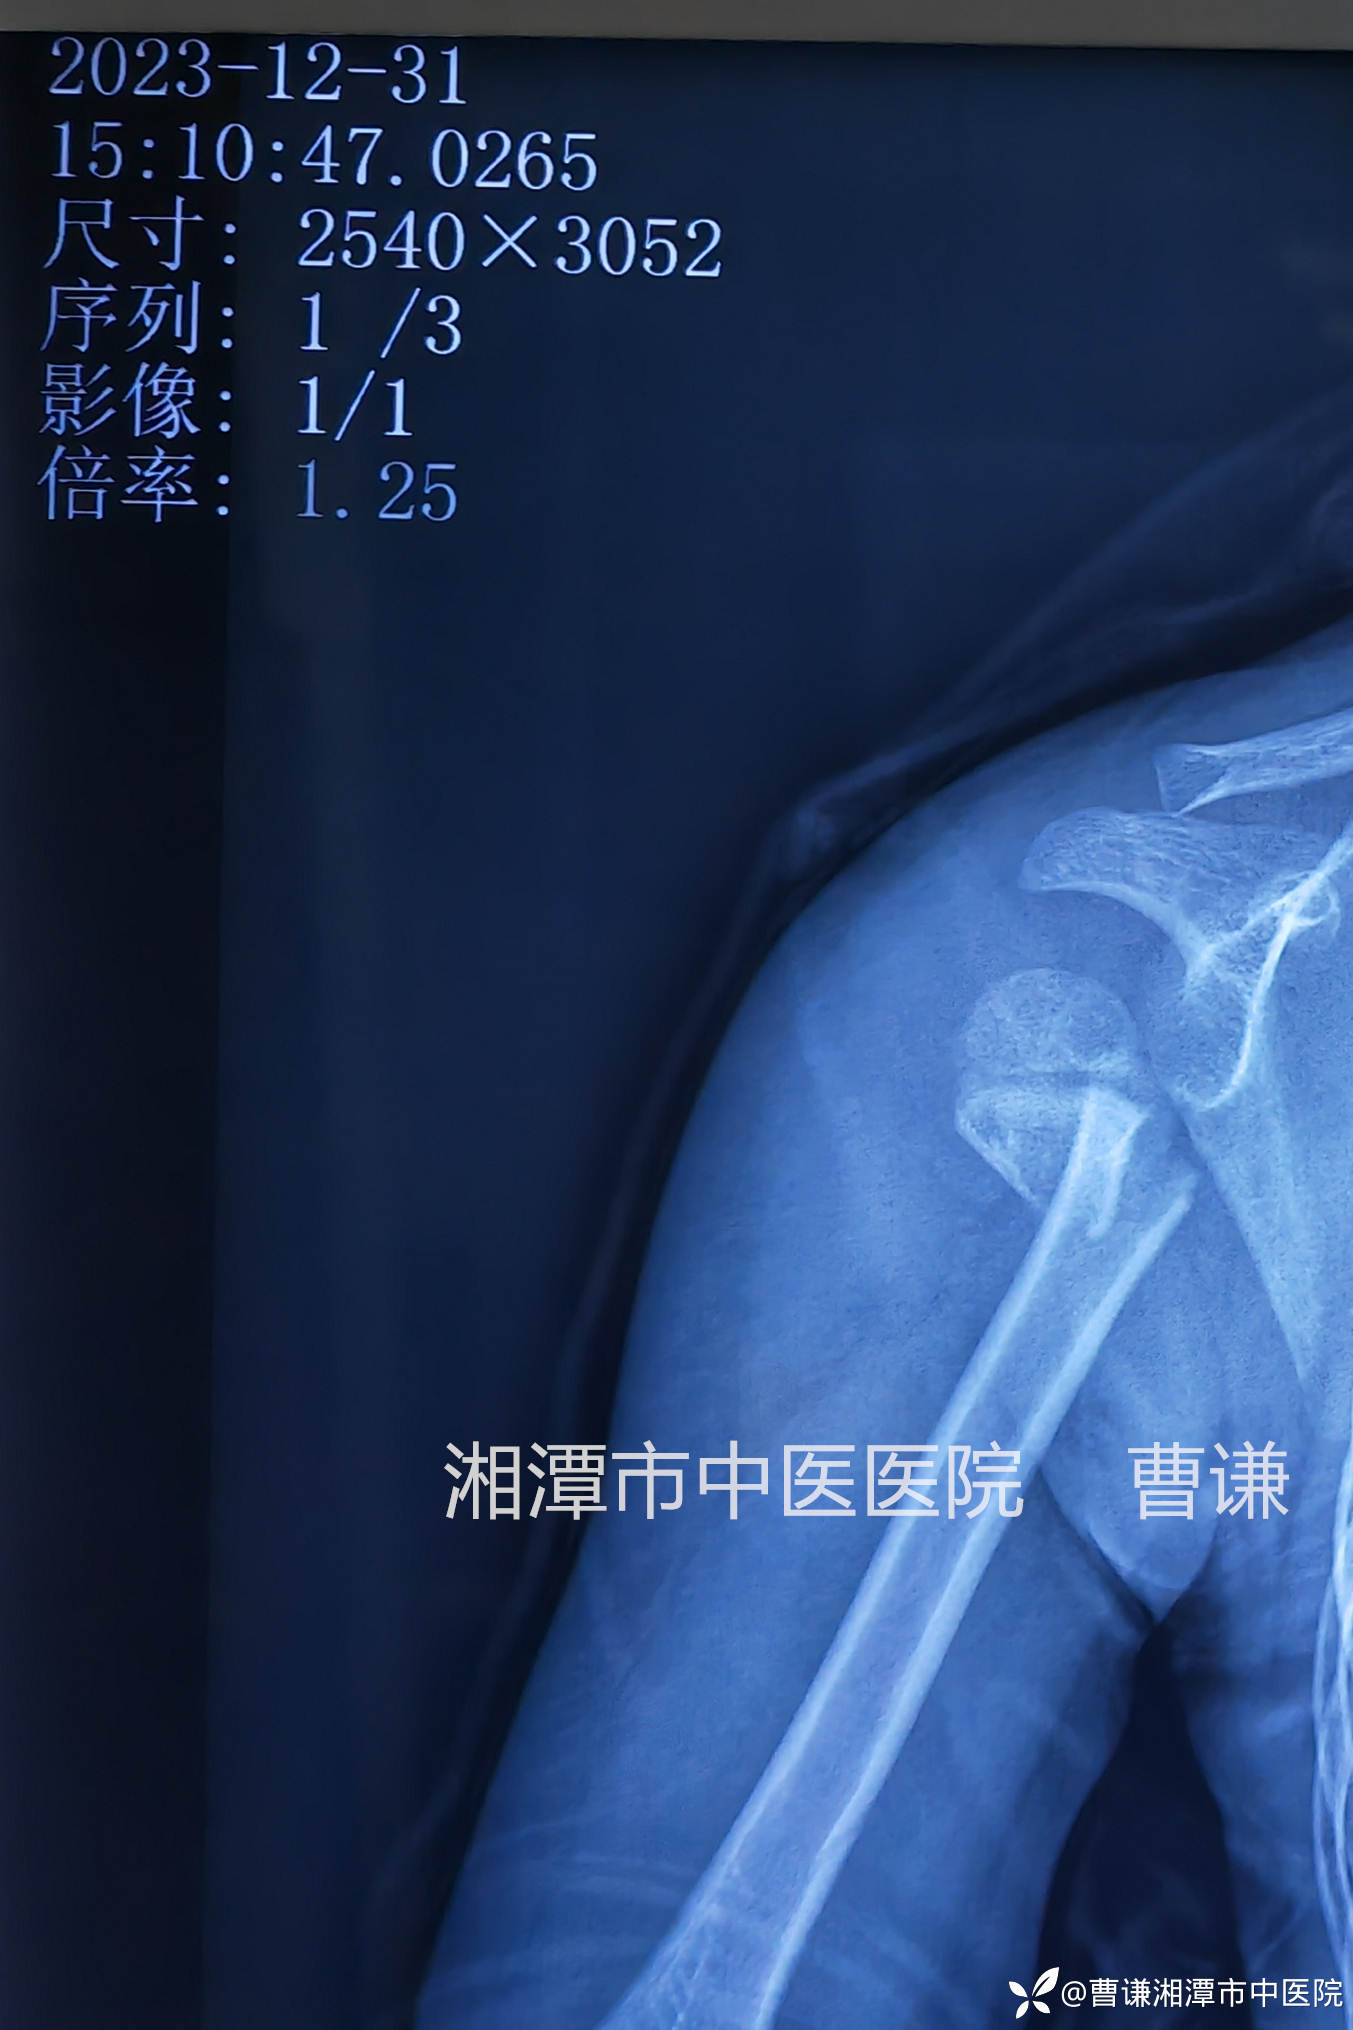

固定完成拍片复查见断端仍然完全错位,肩关节还呈现半脱位的改变。管床大夫赶紧拿着片子给我看,估计心里在嘀咕:主任也是多年的老手了,咋整成这样呢?也可能还在想象我老脸一红,一挥手说:“再整一次!”

我确实是大手一挥,不过是风轻云淡的说:“挺好,继续维持吧!”

由于骨折端出血较多可能导致有瘀血填充到关节囊,形成肩关节半脱位的假象,无需特殊处理,适当进行肩关节被动活动可以加速肩关节半脱位的改善。